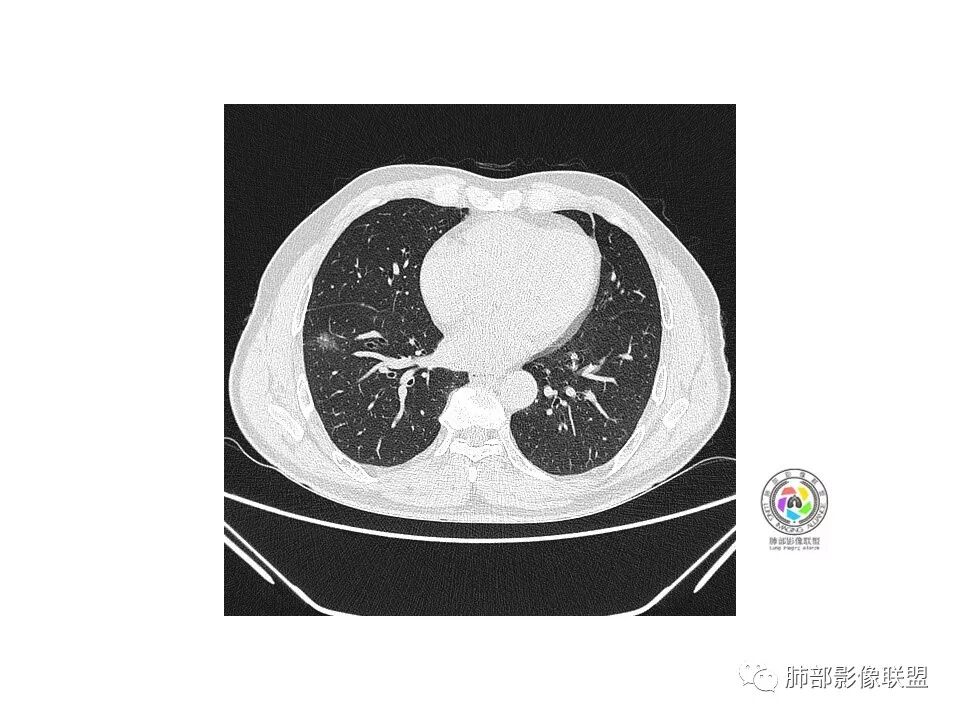

右肺下叶见边界清晰混合磨玻璃密度影,目测内见实性结节小于5mm,有浅分叶,前缘小叶间隔阻挡,月牙铲?胸膜牵拉,老年患者,MIA可能,鉴别炎性病变,抗炎后复查

患者老年男性,以咳嗽 、咳痰3天就诊,胸CT:右肺下叶前基底段mGGO,内可见血管形态改变,细支气管扩张,病灶边界清,边缘可见月牙铲。考虑恶性,腺癌?但建议先抗炎治疗后复查

右肺下叶混合磨玻璃结节,边缘清晰,浅分叶,月牙铲,胸膜牵拉,血管进入,考虑MIA可能,鉴别炎性病变

患者老年男性,咳嗽  咳痰3天就诊。胸部CT:右肺下叶前基底段混合磨玻璃结节,边缘清楚,可见毛刺、胸膜牵拉、血管集束、月牙铲征象。综合考虑微浸润腺癌可能大。

右肺下叶前基底段混合磨玻璃结节,边界清,浅分叶,胸膜牵拉,月牙铲,血管进入,考虑:微浸润腺癌可能性大,抗炎后复查。

老年男性,咳嗽、咳痰3天。胸部CT:右肺下叶前基底段mGGN,边缘清楚,内可见不规则实性成分,病灶可见空泡、毛刺、胸膜牵拉、血管集束征象。考虑MIA可能大,抗炎2W后复查。

老年男性,右下肺前基底段混合GGN,边缘清晰,月牙铲,叶间胸膜牵拉,有轻度收缩力。结合病史抗炎2-3周后复查,消失考虑炎症,变化不大为腺癌。本例总体支持腺癌

老年男性,咳嗽3天,右肺下叶前基底段混合磨玻璃结节,形态不规整,相邻胸膜凹陷,可见血管影,考虑腺癌可能性大,不除外炎症可能,建议抗炎1~2周,1个月复查胸部CT。

右肺下叶mGGN,内部结构紊乱,可见小点状高密度影,边缘清晰,小叶间隔阻挡,轻度收缩力,考虑MIA,常规飞一会20天复查。

老年男性,右肺下叶前基底段GGN,界清,内部血管结构杂乱,叶间胸膜牵拉。考虑恶性,早期腺癌可能,建议抗炎治疗后复查对比。

右肺下叶前基底段见一磨玻璃结节影,呈分叶状,边缘部分模糊,与胸膜间有长条索粘连,内有增粗的血管影,后者边缘毛糙,考虑微浸润性腺癌,建议抗炎治疗后复查

老年男性,右肺下叶前基底段斜裂旁可见单个混合型磨玻璃结节mGGN,边缘清,内部结构紊乱,进入的血管增粗,支气管关系不好判断,斜裂侧可见牵拉,常规考虑微侵腺癌MIA,建议先抗炎后复查及手术干预。

老年男性,咳嗽咳痰3天。MGGN,边缘见月牙铲、胸膜牵拉,血管移动联通?冠状位隐约可见支气管穿行,考虑MIA,重建冠位可见结节比较靠近叶裂,可积极手术处理。

老年男性,右S8混合磨玻璃结节,边缘尚清晰,局部凹陷,叶间胸膜牵拉,考虑MIA可能大,建议抗炎治疗10天,6-8周后复查

右肺下叶混合磨玻璃密度结节,有月牙铲,内可见血管,血管移动联通,常规消炎复查,还存在考虑AIS-MIA

患者老年男性,右下肺前基底段靠近胸膜侧可见一个mGGO结节,边缘清淅,可见分叶征及月牙铲,小结节病灶胸膜牵拉明显,首先考虑MIA可能性大。

右肺下叶mGGO,边缘清晰,浅分叶,内血管影增粗,见点状实性成分,小支气管牵拉扩张,考虑MIA,建议抗炎后复查。

右肺下叶前基底段mGGN,边界清晰,内部结构杂乱,见网格空泡感,月牙铲,浅分叶及胸膜牵拉,倾向MIA。

右肺下叶GGO,边缘清晰,有月牙铲,有血管进入,内部结构紊乱,胸膜牵拉,考虑MIA,常规建议抗炎治疗后复查。

右肺下叶磨玻璃结节,边界清晰,边缘有分叶及月牙铲,并可见轻度胸膜牵拉,收缩力弱,有血管移动联通征,而且病灶内血管影轻度增粗,实性成分很少,考虑AIS,可以让子弹再飞一会,或常规抗炎治疗后复查。

右肺下叶前基底段磨玻璃小结节,其内血管稍增粗,边缘见分叶、月牙铲,考虑ais,炎性结节不排